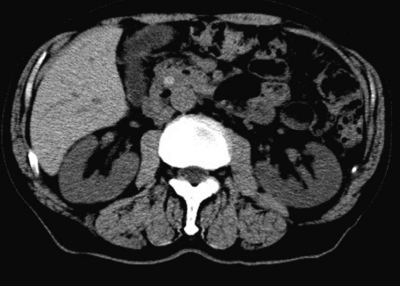

血液所見:白血球 17,600。血液生化学所見:総ビリルビン 6.9 mg/dL、直接ビリルビン 4.2 mg/dL、AST 371 U/L、ALT 297 U/L、ALP 531 U/L(基準 115〜359)、γ-GTP 237 U/L(基準 8〜50)、アミラーゼ 52 U/L(基準 37〜160)。CRP 16 mg/dL。腹部超音波検査で胆囊壁に異常を認めない。腹部CTを別に示す。